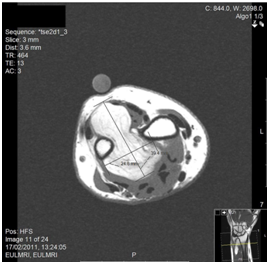

A 60year-old female secretary presented with swelling on the dorsal and volar aspects of her left non-dominant distal forearm and a mild ache at the base of the thumb. The lesion was non-tender and mobile, causing no functional impairment. Past medical history included hypercholesterolaemia, hypertension, gastroesophageal reflux and allergic rhinitis and easy bruising was reported. Ultrasound confirmed a well-defined, hyperechoic lesion, avascular on colour flow imaging, consistent with an intramuscular lipoma.MRI confirmed a 4x2.5x5.5cm lobular fatty tumour of the distal forearm, bridging the anterior and posterior compartments (Figure 3), extending to the distal radioulnar joint, close to the interosseous nerve. Fine-needle aspiration cytology demonstrated benign spindle and epithelioid cells. The possibility of a benign fibrohystiocytic tumour, or low-grade malignancy was raised and synovial sarcoma thought unlikely. Surgical exploration under was performed via a volar approach. A lipomatous lesion deep to the flexor tendons displaced the ulnar artery and nerve. The lesion penetrated the interosseous membrane, which required division for en masse excision. Histopathology reported a benignlipoma. A full functional recovery was noted, no recurrence at two years.

Figure 3 Axial T1 MR Image of the left forearm demonstrating the mass of lipoma crossing the interosseous membrane between radius and ulna.